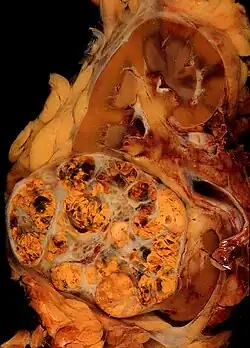

L'examen fondamental pour le diagnostic est le scanner abdominal. L'examen visualise la tumeur, ses rapports avec les organes adjacents ainsi que la présence ou non de métastases, tout au moins abdominales. L'examen est suffisamment discriminant pour conduire directement à une chirurgie rénale. Le diagnostic positif de cancer du rein sera ensuite porté sur l'examen de la pièce opératoire. Le bilan diagnostic initial permet de déterminer l'extension de la tumeur, la présence de métastases et donc de définir une stratégie thérapeutique précise. Une IRM abdominale est parfois utile pour préciser l'extension de la lésion dans la loge rénale et déterminer la présence éventuelle d'un caillot tumoral dans la veine rénale et la veine cave inferieure.

Anatomopathologie

Elle est basée essentiellement sur l'examen anatomopathologique de la pièce chirurgicale d'exérèse, la biopsie n'ayant que peu d'utilité. La classification anatomo-pathologique des tumeurs du rein est la classification UICC.

La thrombose de la veine rénale pouvant remonter jusqu'à la veine cave inférieure, voire jusqu'à l'atrium droit, se voit dans 10 % des cas[14].